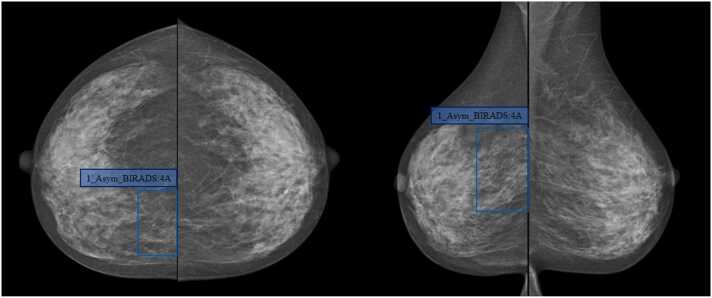

Fig. 3.

Case 1, Female, 46-year-old, uneven dense breast (ACR Type C), which was evaluated as BI-RADS 4A after the DL detected the asymmetry in the upper quadrant of the right breast (blue box); During the operation, there was a mass near the sternum at 2 points in the upper quadrant of the right breast with a size of 3.5 cm × 5.6 cm, clear boundary, hard texture, and no coating. Pathological results: invasive non-special type carcinoma.